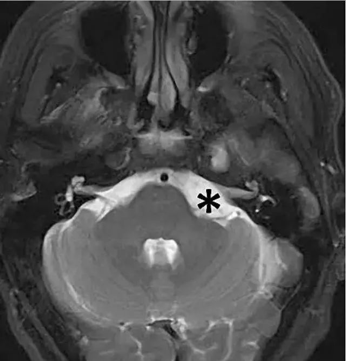

桥小脑角区(Cerebellopontine angle,CPA)是由前内侧的桥脑外缘、前外侧的岩骨内缘及后下方的小脑半球前外侧缘构成一个锥形窄小的空间,而锥交则正于岩骨尖。此区的重要性在于集中了听神经、面神经、三叉神经及岩静脉等。

图 1 *号所标位置附近即为桥小脑角区,此处可见

桥小脑角区多为轴外肿瘤,以听神经瘤常见,以及脑膜瘤,三叉神经瘤,另外可见胆脂瘤,蛛网膜囊肿,血管母细胞瘤,动脉瘤,海绵状血管瘤,转移瘤,以及发生于小脑及脑干的脑内肿瘤突入桥小脑角区。